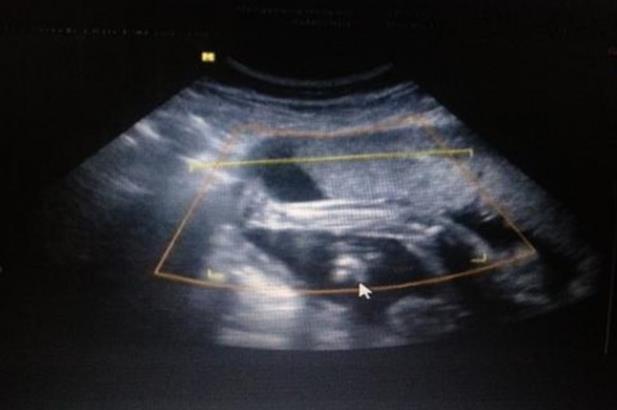

三周体重没长,宝宝却重了

今天去产检了,结果让我很开心,终于头位了,由于脐带绕颈一直顺其自然没敢做操纠正,只是天天摸着肚子对宝宝说,让他转下去,事实上对宝宝说的话也是安慰我自己,哈哈,产检时医生在我肚子上按了半天,她说不确定是不是已经头位了,我去,被她按的肚子都痛了,后来让我去做个B超看看,B超结果显示,头位,但还是脐带绕颈一周,宝宝偏大两周,我郁闷了,三个星期了我体重没长还是57,宝宝是怎么长的,现在都5斤1两了?平时宝宝胎心都是130左右,今天按肚子按久了,他也不舒服一直动,不过那么久以来我是第二次这么开心了,终于头位了头位了